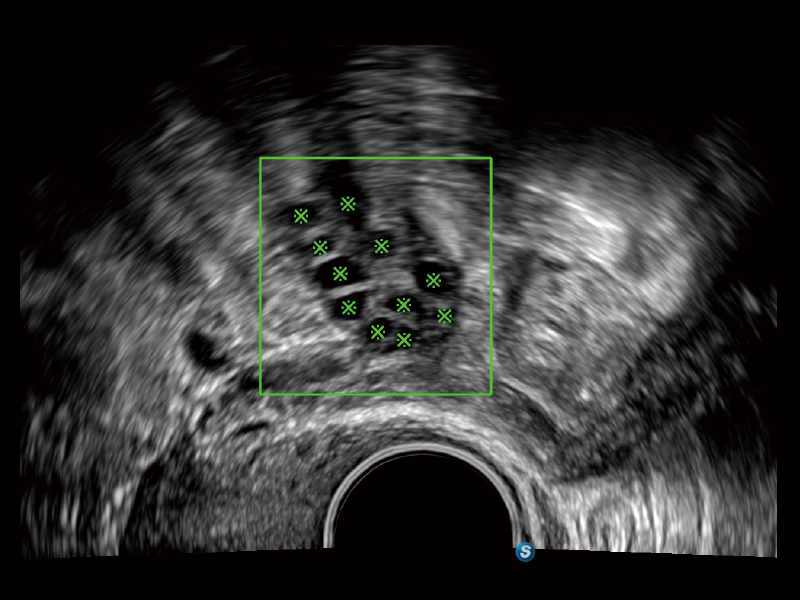

通過創(chuàng)新的Matrix E自適應(yīng)濾波算法,能有效濾除軟組織和噪聲信號(hào),最大限度保留超低速微細(xì)血流的信號(hào);結(jié)合超長時(shí)間域算法,極大提升細(xì)微血流的敏感性和空間分辨率,更真實(shí)的反應(yīng)組織、包塊的血流灌注情況。

夢(mèng)溪?P80以“關(guān)愛女性”為基石,提供全方位的解決方案,量身定制以滿足女性的健康需求,涵蓋婦科、生殖健康檢查、產(chǎn)前篩查及產(chǎn)后康復(fù)等領(lǐng)域。